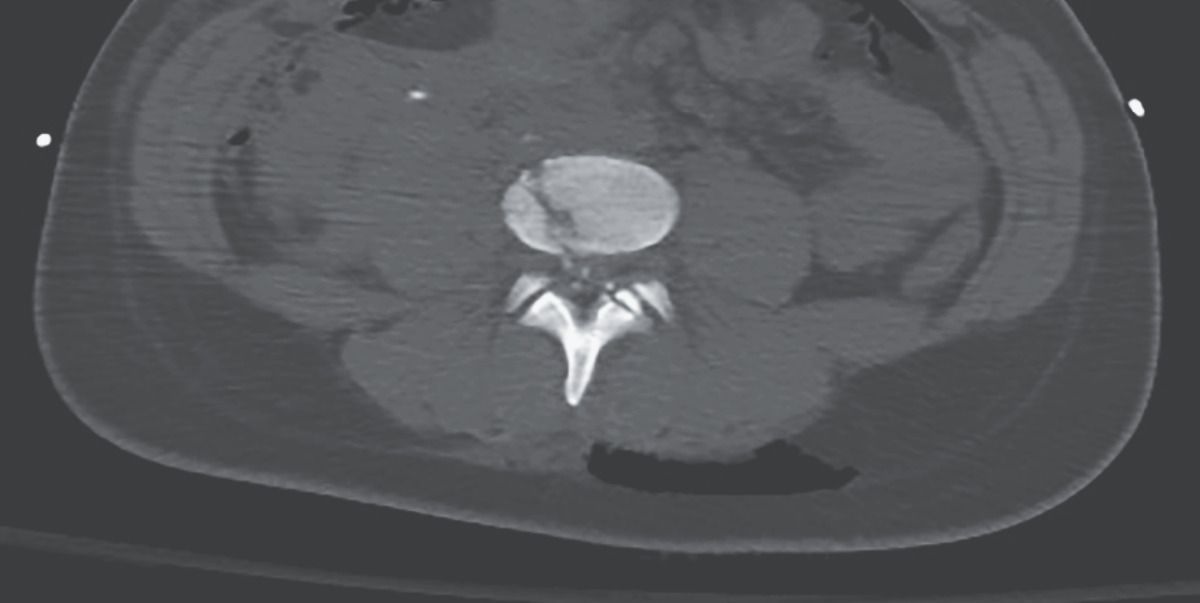

A 19-year-old woman presented to the emergency department with a single gunshot wound to the abdomen. Her blood pressure was 99/58 mm Hg, and her heart rate was 93 beats per minute. On examination, she was unable to move her legs and had complete loss of sensation below the knees. A computed tomographic angiogram showed active extravasation from the inferior vena cava as well as a comminuted fracture extending through the L4 vertebral body, with bone fragments seen in the spinal canal. The patient was taken to the operating room, where she underwent exploratory laparotomy and vascular repair. Within 24 hours after presentation, she also underwent transforaminal lumbar interbody fusion of the L3–L4 and L4–L5 vertebrae. Comminuted fractures (those in which a bone breaks into more than two fragments) are typically caused by high-energy traumatic events such as gunshot wounds. One month later, the patient had regained some sensation and movement in her feet. She was discharged to a rehabilitation facility.